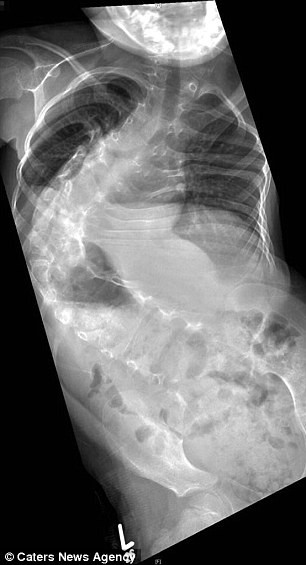

Ellisha Hockham, 11 tuổi, được chẩn đoán là bị cong vẹo cột sống khi vẫn còn trong bụng mẹ. Khi mang thai được 20 tuần, cặp vợ chồng Sally và Shane sống tại Ipswich (Anh) còn được khuyên nên bỏ thai vì xương sống của thai nhi đang bị gập 80 độ và bé có thể sẽ không sống quá 10 tuổi.

Muốn cho con mình một cơ hội tốt nhất có thể, cặp vợ chồng này đã từ chối không nghe theo lời khuyên của bác sĩ. Khi mới 10 tháng tuổi, bé Ellisha đã được phẫu thuật lần đầu tiên. Những năm đầu đời của cô bé phải sống trong cảnh bó bột nhưng khi lên 6 tuổi, xương sống bị cong gập xấu nhất thành 170 độ, bác sĩ cho biết nếu không phẫu thuật thêm thì xương sống sẽ dần nghiến nát cô bé.